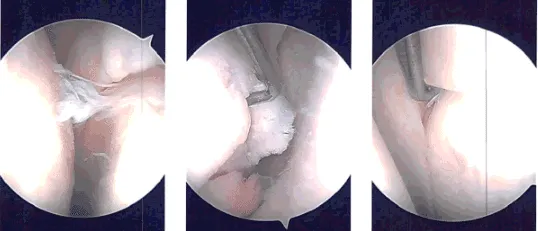

El portal medial se realizó en visualización usando una aguja espinal. Se introdujo una afeitadora y se realizó desbridamiento del cuerno anterior del menisco medial, así como la lesión osteoartrítica y la condroplastia por abrasión del cóndilo femoral medial. Se introdujo un endoscopio en la zona intercondilar donde se encontró intacto el LCA.

El endoscopio se introdujo en el compartimento lateral, donde había deshilachado difuso en el margen medial del menisco lateral. También había una rotura del cuerno anterior del menisco lateral. El afeitado y desbridamiento del menisco lateral se realizó utilizando una maquinadora.

Tras todo el afeitado, se introdujo la cámara en la articulación patelofemoral donde se observaron los cambios osteoartríticos de grado 3 a 4 de la tróclea y se realizó condroplastia por abrasión.

Ahora, el endoscopio se introducía por la puerta medial y se introducía por la puerta medial, y se realizaba un desbridamiento adicional del menisco lateral usando una afeitadora, upfitters, backbiter y biters izquierdos.

Tras equilibrar la parte medial del menisco lateral, se realizó el resto del examen y se tomaron los hallazgos.